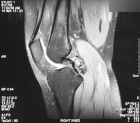

J.G. - 22 year old female with right knee pain

Zoom image: Radiological image Radiological image.